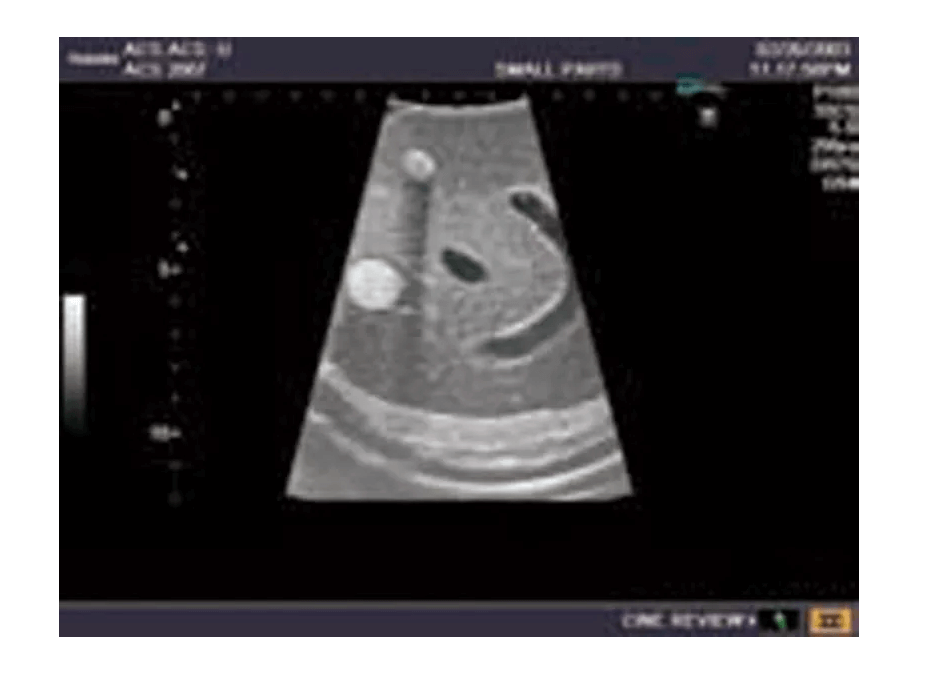

Das Ultraschall-Modell für Sonografie ist speziell für die Ausbildung von Anfängern und die Demonstration durch Fachleute konzipiert. Es bietet eine detaillierte und realistische Darstellung der Anatomie des Abdomens, einschließlich der Leber, Gallenwege, des Pankreas und der Nieren. Das Modell erfüllt die höchsten Anforderungen an eine exzellente Ausbildung und ermöglicht die Durchführung von offenen intraoperativen Sonografien sowie laparoskopischen Untersuchungen, um etwaige Läsionen und Steinbildungen zu prüfen. Es umfasst eine Vielzahl von Läsionen wie Gallensteine, Zysten und Tumore, die in den verschiedenen Organen simuliert sind, um realistische Übungsmöglichkeiten zu bieten.

Realistische Darstellung der Anatomie von Leber, Gallenwegen, Pankreas, Milz und Nieren

Modell enthält eine detailgetreue Darstellung von Gefäßstrukturen wie Aorta, Vena cava, Vena portae und Nierengefäßen

Die Simulation von pathologischen Befunden wie Tumoren, Zysten und Steinbildungen ermöglicht eine umfassende Vorbereitung auf die Ultraschalldiagnostik